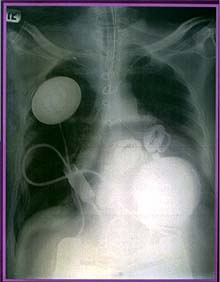

El corazón artifical, Abiocor, fue fabricado por la empresa estadounidense Abiomed, cuyo portavoz explicó después de la operación que "el implante deberá funcionar como mínimo seis meses y que si el paciente sobrevive los dos primeros meses, entonces otras cinco personas serán sometidas a trasplantes de corazón artificial".

El nuevo prototipo de corazón artificial, cuyo tamaño es similar al del corazón humano, funciona como un corazón natural, con dos bombas diferenciadas que mueven la sangre por el cuerpo a razón de hasta ocho litros por minuto cada una.